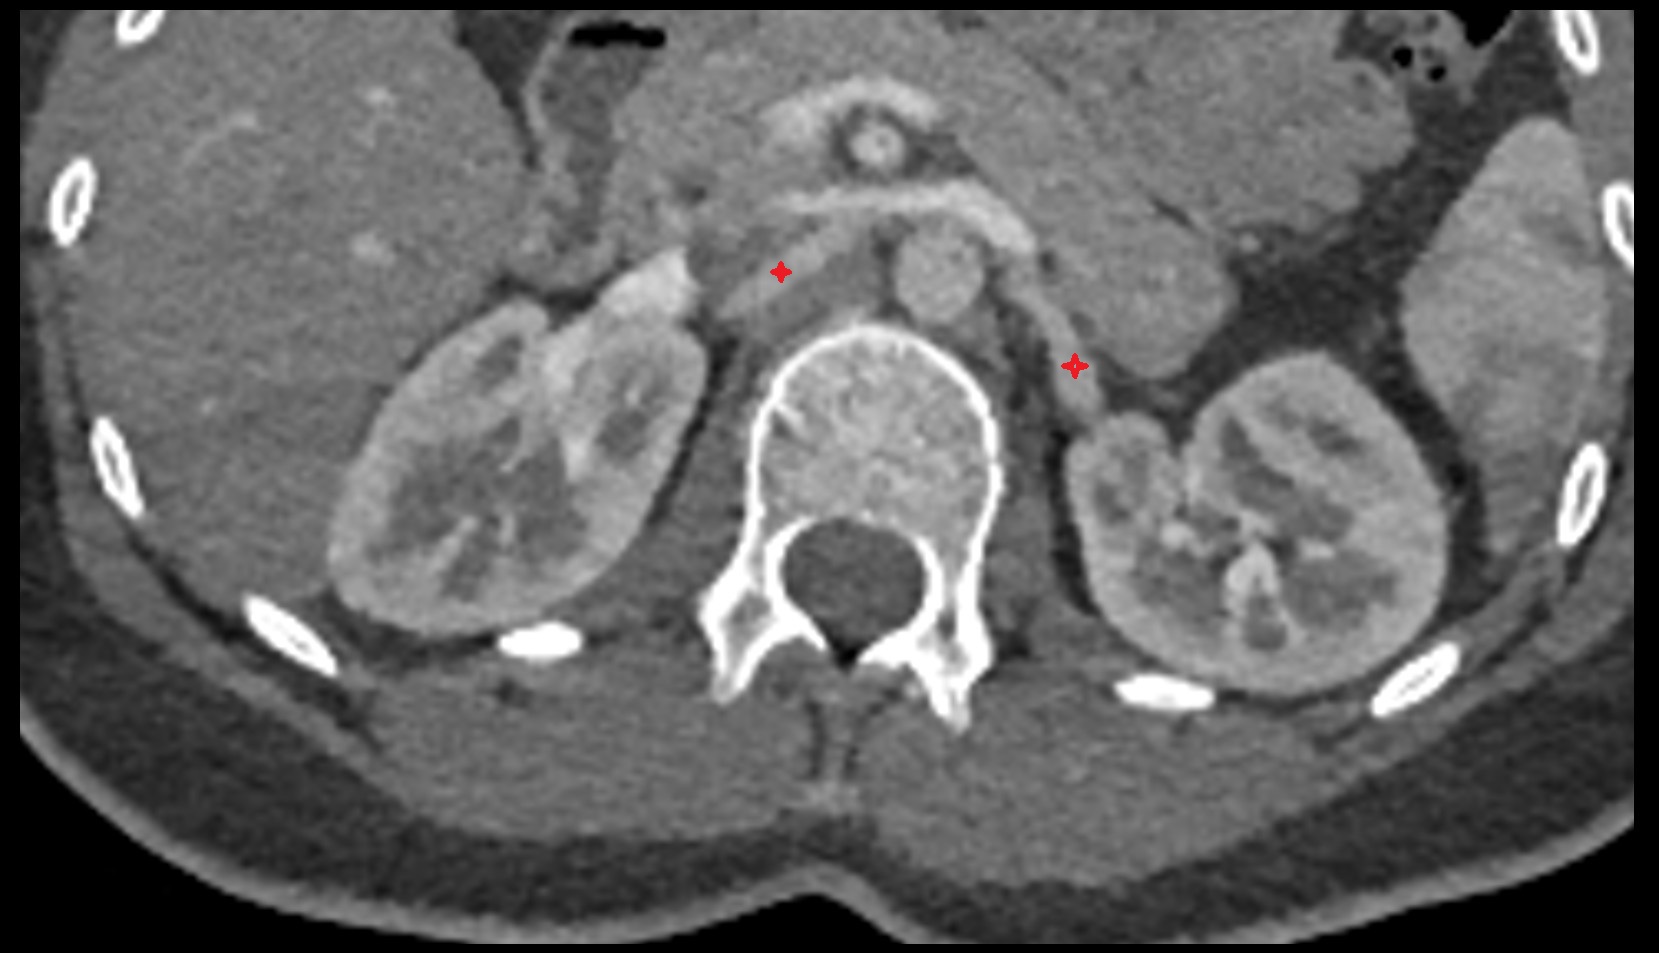

- kidneys

- Right kidney

- Left kidney

- Kidney cortex (Renal cortex)

- Renal medulla

- Renal pyramids

- Ureters

- Renal artery

- Renal vein

- Left renal vein

- Right renal vein

- Left renal artery

- Right renal artery